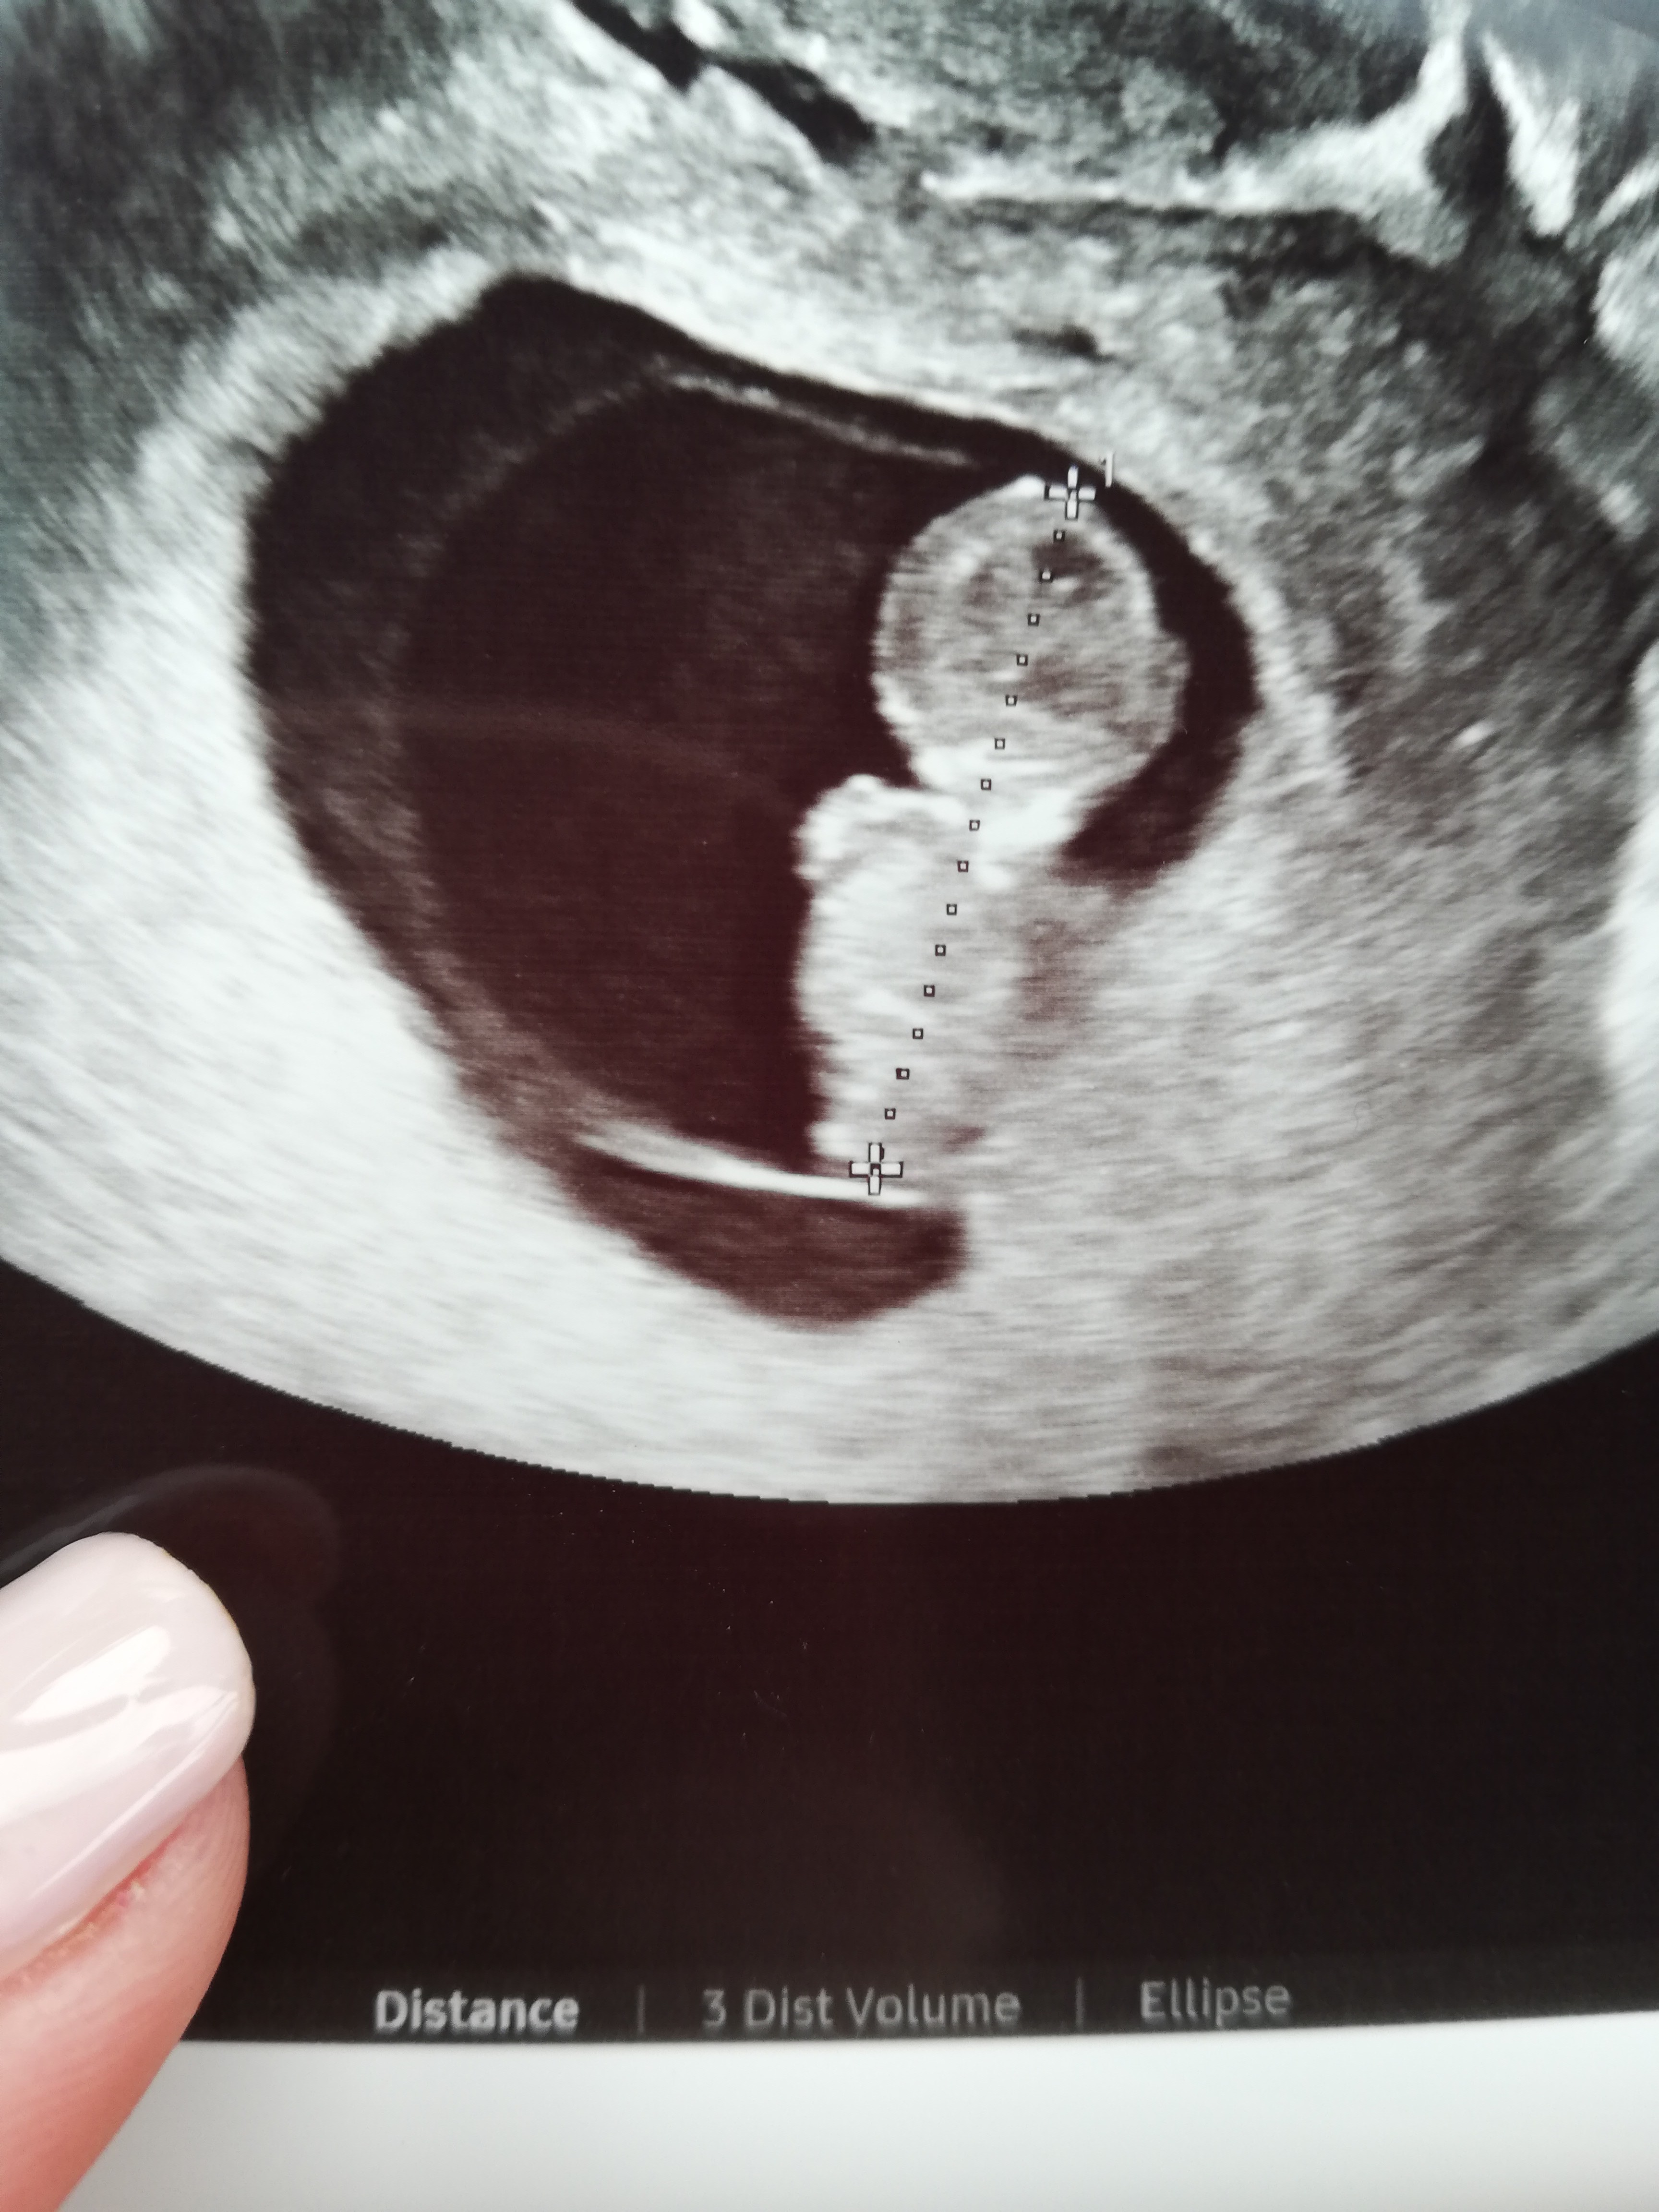

Cześć 💕💕 za tydzień prenatalne serduszko bije 140

• IMG_20210924_091255.jpg

IMG_20210924_091255.jpg

1,7 MB · Wyświetleń: 115

Kurczę mi teraz prenatalne wyjdą 13+1..

Jak się umawiałam to wychodziło 12+4, ale kolejne pomiary zweryfikowały rozmiar i wiek ciąży 😁

Mam nadzieję że już nie przyspieszy..